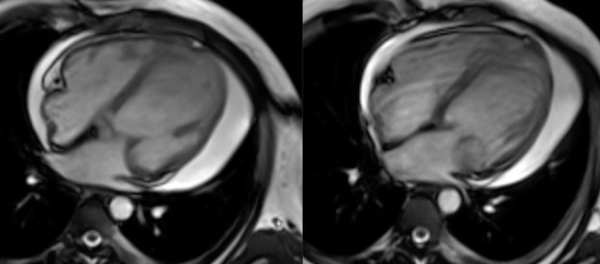

This 32 years old man came with breathlessness. Echo showed a mass. An MRI was done.

The video explains the rest. Free to view, but you need to subscribe with your email ID.